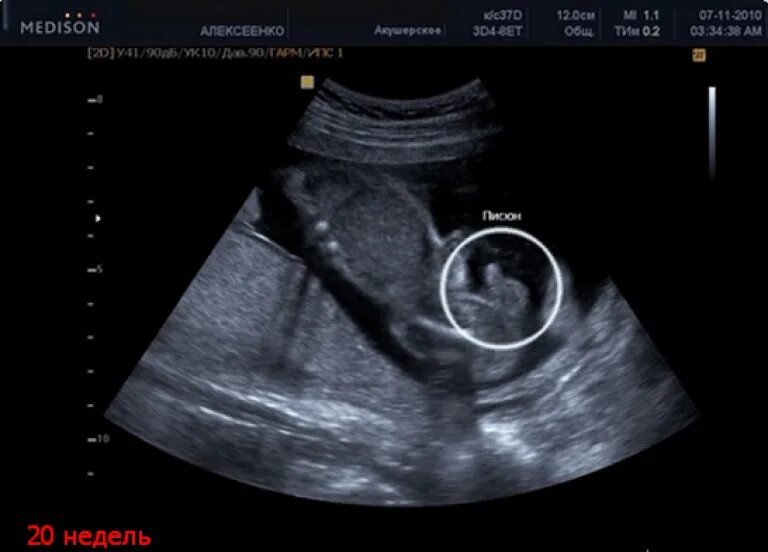

Плод девочка